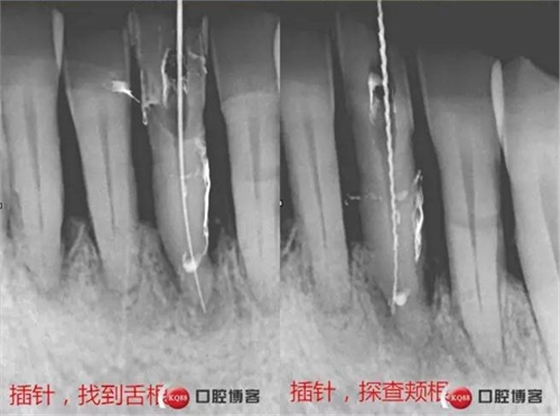

處理:上橡皮障,31開髓,測(cè)工作長(zhǎng)度17mm,含氯沖洗液沖洗,機(jī)擴(kuò)至04錐度30#,超聲蕩洗,一次性根充。33-43牙齒鄰接處super bond粘結(jié)固位,行松牙固定。調(diào)合。拍根充術(shù)后片,未達(dá)根尖,懷疑遺漏根管,去除根充物后,繼續(xù)探查根管,找到舌側(cè)根管,測(cè)長(zhǎng)度20mm,時(shí)間原因,未行擴(kuò)根,氫氧化鈣暫封。

處理:31去暫封,手用銼疏通根管,沖洗,機(jī)擴(kuò)至04錐度30#,超聲蕩洗,封維塔,拍片。